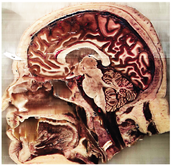

Table 2, Table 3, Table 4 and Table 5 present the results obtained through the multi-objective optimization image enhancement approach. Specifically, Table 2 and Table 3 show the results for natural images, while Table 4 and Table 5 display medical images. The tables are organized as follows: the first and second columns list the image names and their corresponding original, unenhanced versions. The third to fifth columns showcase the selected points from the Pareto front, representing the maximum contrast, knee point, and maximum detail, in that order. The final column illustrates the obtained Pareto front through the optimization process, with red, green, and orange points indicating the images that achieved maximum contrast, knee point, and maximum detail, respectively.

Table 4.

Medical image results—1.

As observed in the results, the images extracted from the Pareto front significantly maximize contrast and detail compared to the original images. In all study cases, the original image is dominated by the solutions extracted from the fronts, demonstrating the approach’s effectiveness in improving visual quality. However, the differences among the three enhanced images for each problem require a more detailed analysis.

For medical images, there are instances where differences are more perceptible. For example, in the Medical3 image, the maximum contrast solution makes it difficult to visualize the internal details of the basophil (a white blood cell highlighted in the box), which could result in a less accurate interpretation. In contrast, the knee and maximum detail solutions provide a clearer view of the interior of the white blood cell. Similarly, in the Medical5 image, the maximum contrast solution highlights the hand and arm bone structures. However, the maximum detail image offers a more precise view of the internal structures within the bones (see the highlighted region), which is crucial for a more detailed evaluation. Another notable example is the Medical8 image, where the maximum detail solution offers a more detailed view of the internal structure of the eosinophil (another type of white blood cell). However, the maximum contrast image improves the visibility of red blood cells. As shown in the yellow box, this solution reveals a red blood cell that is nearly imperceptible in the other solutions. An interesting case is the Medical6 image, where only a few non-dominated solutions are present on the Pareto front. Despite the similarities among the preferred solutions, the nodules are much more perceptible in the enhanced images than in the original image, as observed in the highlighted region.